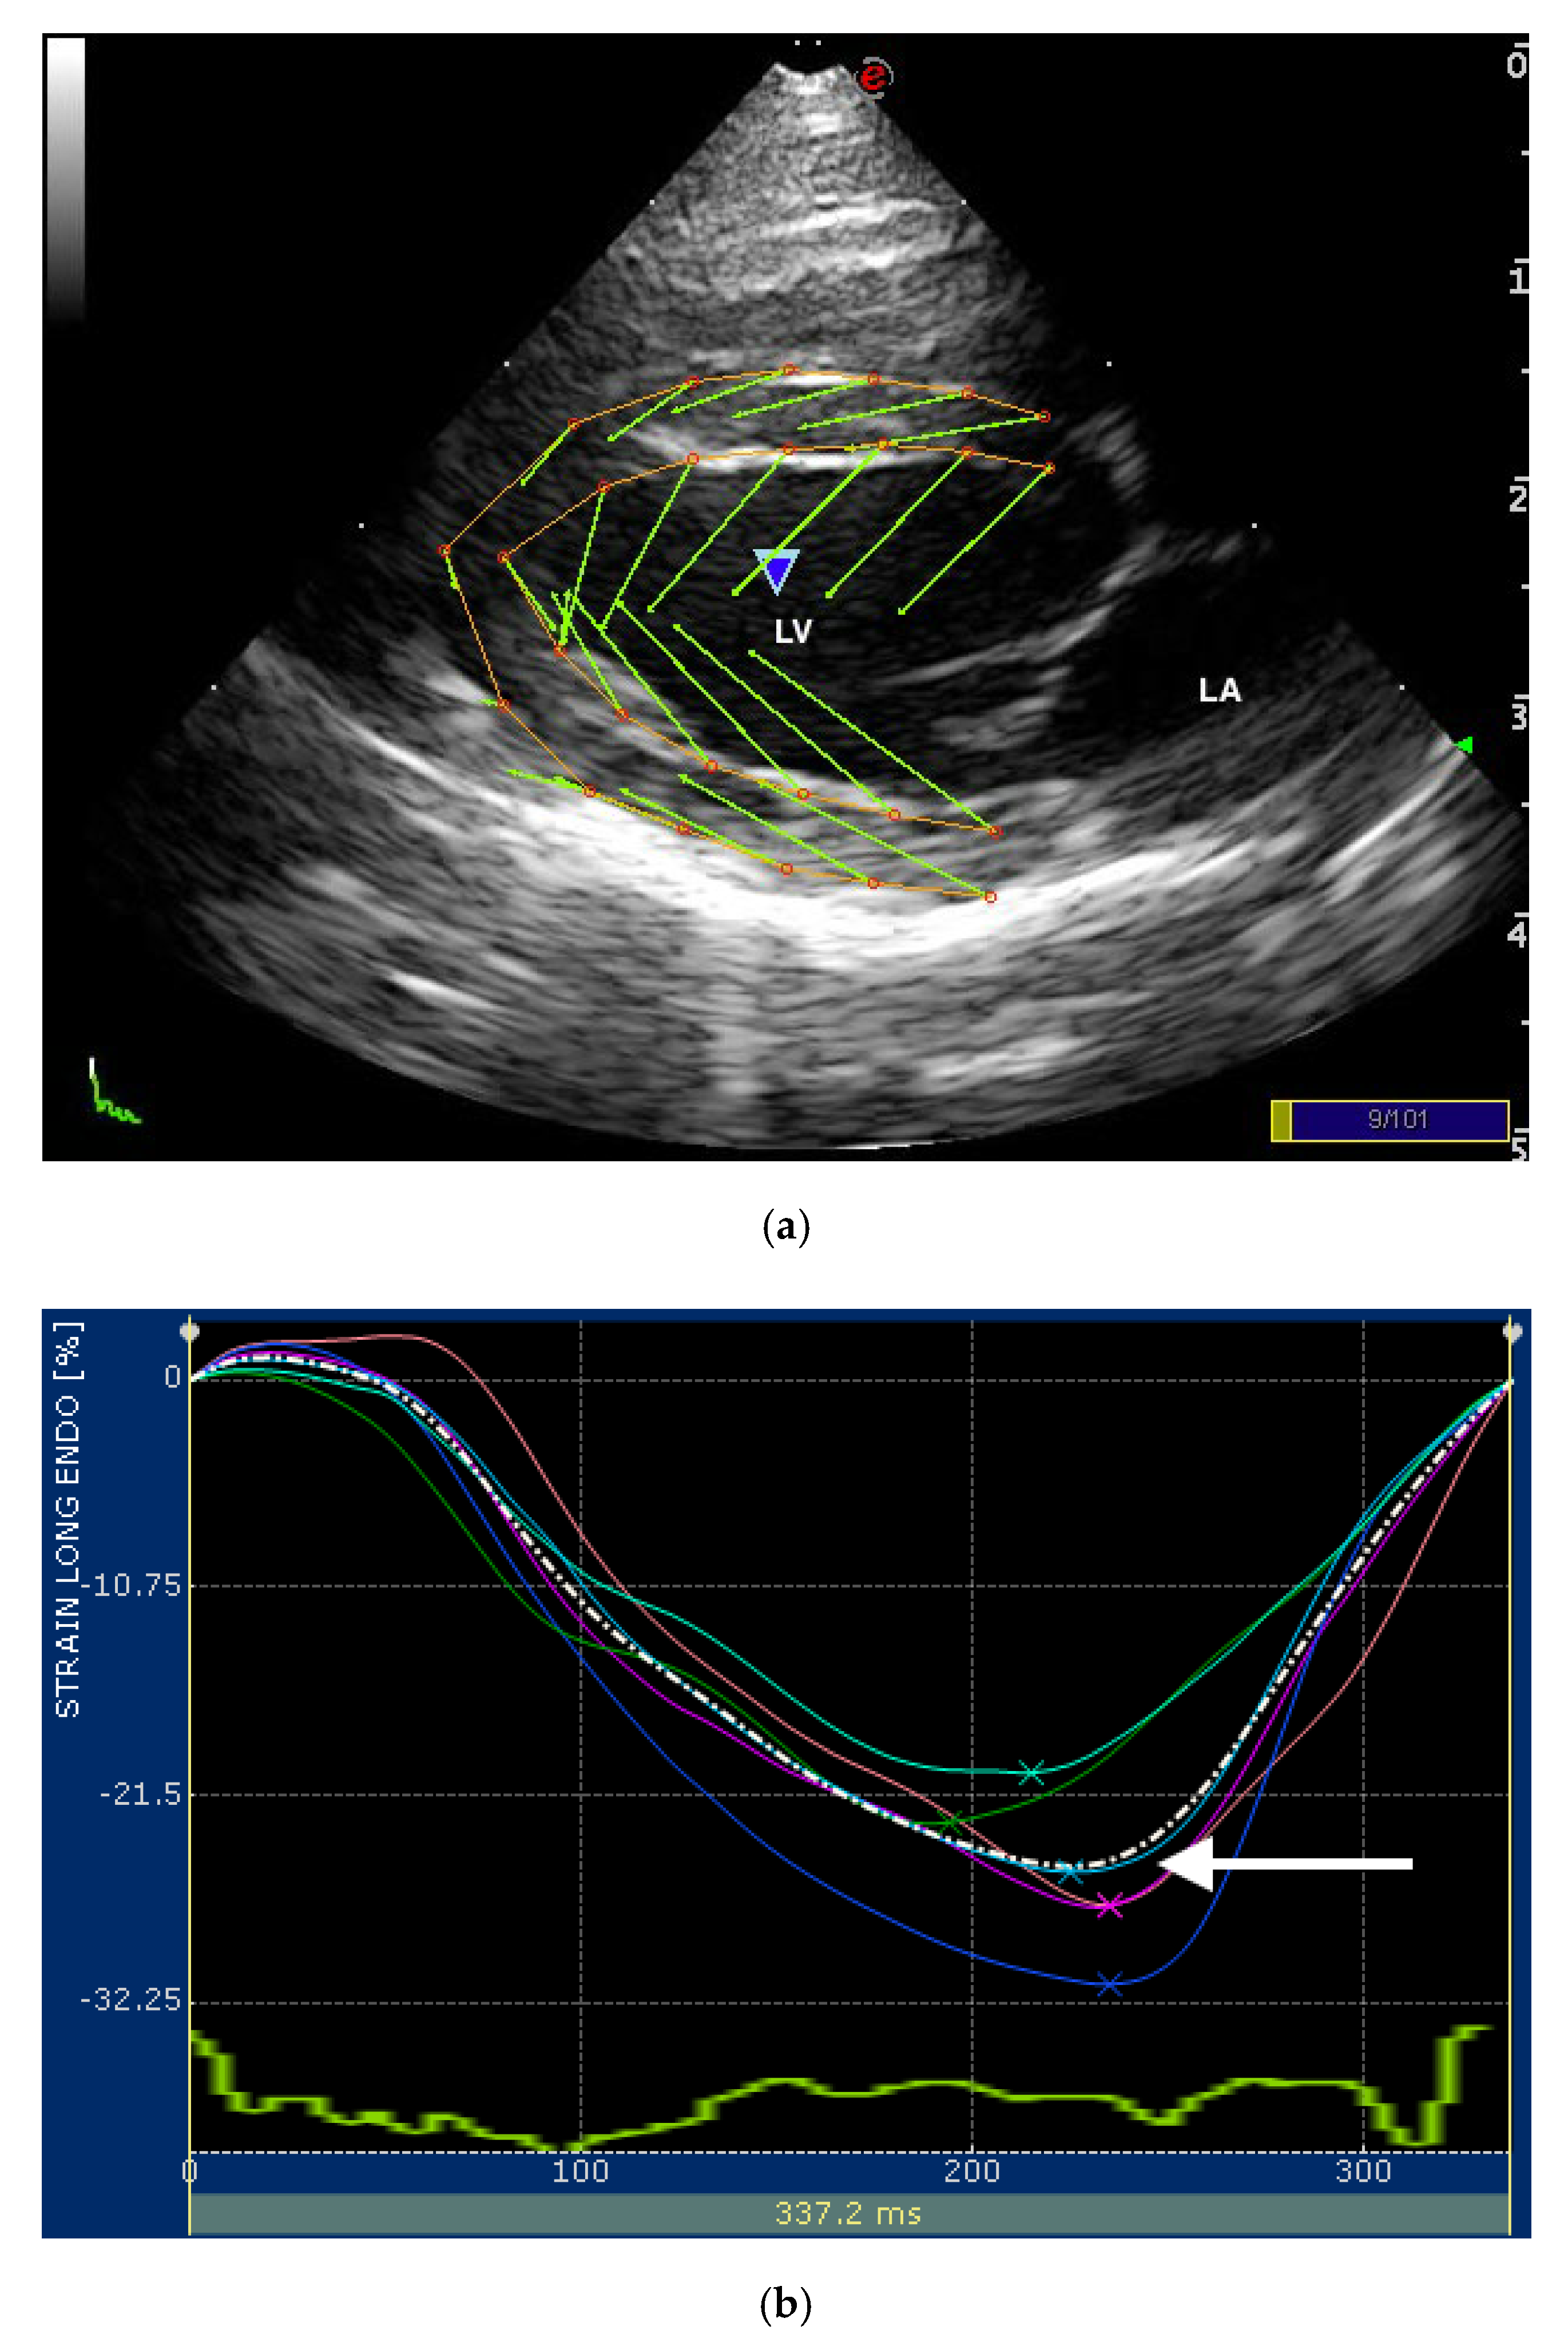

Twodimensional speckle trackling echocardiography (A) Normal cat (B How Is An Echocardiogram Performed On A Cat what is an echocardiogram for pets? Furthermore, echocardiographic examination of a cat is not a simple or easily performed test, full of pitfalls for the inexperienced. the best test for diagnosing hcm in cats is an echocardiogram (echo). An echo shows your veterinarian or veterinary cardiologist whether your. our cardiologist at the long beach animal hospital is. How Is An Echocardiogram Performed On A Cat.

From www.mdpi.com

Veterinary Sciences Free FullText Assessment of Longitudinal Left How Is An Echocardiogram Performed On A Cat An echo shows your veterinarian or veterinary cardiologist whether your. echocardiography is unquestionably the most useful tool for the diagnosis of heart disease in cats; Furthermore, echocardiographic examination of a cat is not a simple or easily performed test, full of pitfalls for the inexperienced. Just as in humans, an echocardiogram is a diagnostic tool we use to examine. How Is An Echocardiogram Performed On A Cat.